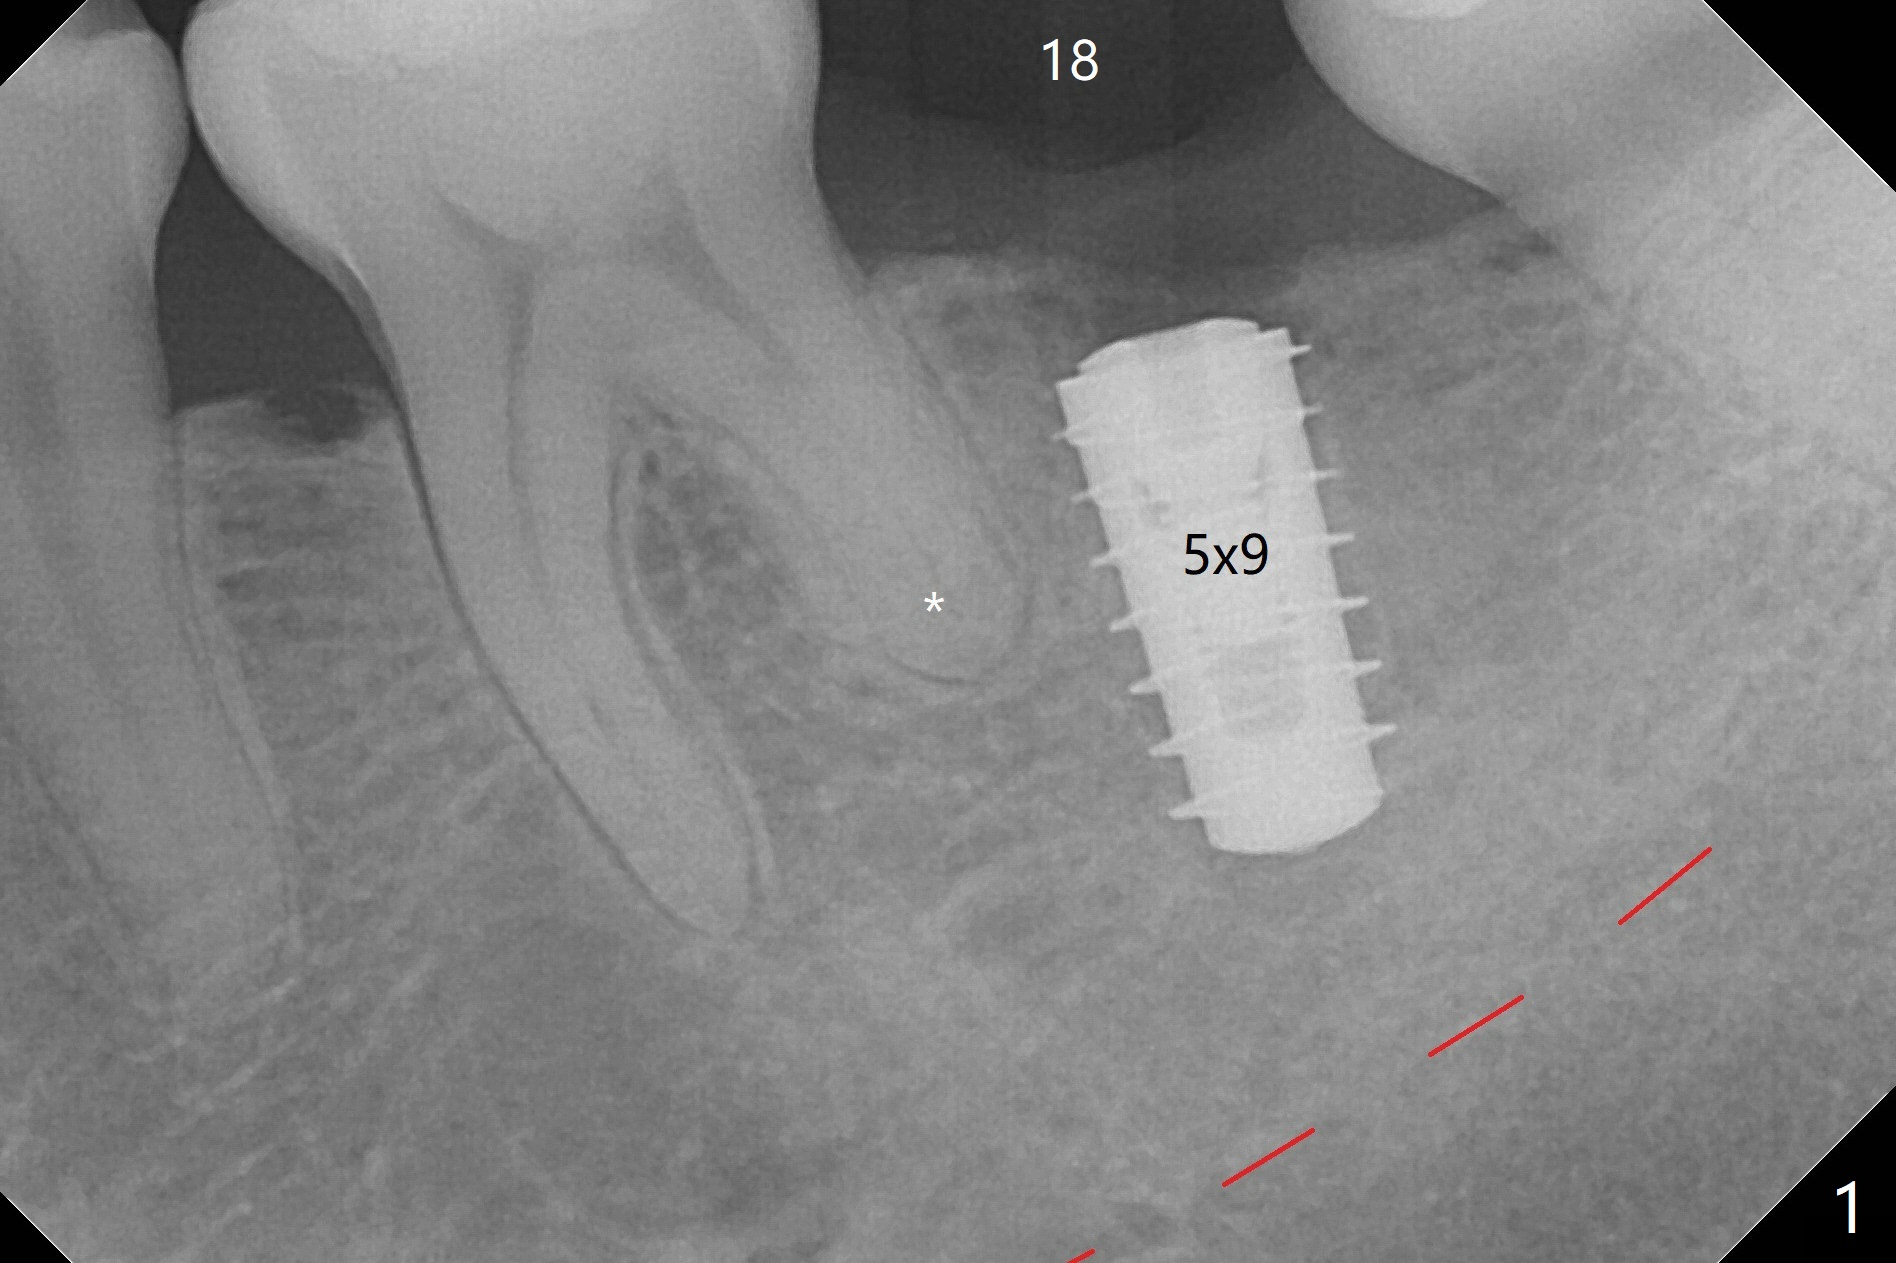

In contrast to #2 implant, the insertion torque of a 5x9 mm implant at #18 (Fig.1) is less than 10 Ncm because of depth difference between 2 implant systems. The design is for 5x10 mm. In fact each drill has its inherent 1.2 mm long tip. The 8.5 mm drilling depth is enough for 9 mm implant. The 2nd potential problem is that the implant may truncate a branch from the Inferior Alveolar Canal to the distal root of the 1st molar (Fig.2 (original design)). Ideally the implant should be placed distal and tilted mesial and short in length (Fig.3 (design to be improved)). A smaller implant may also help. A layer of new bone forms on the top of the implant 3 months postop (Fig.4 *). It is removed with surgical handpiece. After use of 5.6 mm profile drill, a 6x4 mm healing abutment is placed with minimal clearance from the mesial crest (Fig.5 *). A month later, a 5x4(3) mm pair abutment is seated apparently completely (Fig.6). A crown is delivered nearly 6.5 months postop (Fig.7 (mesial contact light)). The implant is subcrestal (*).